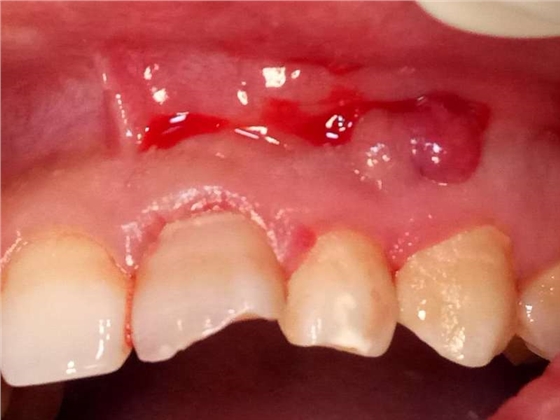

死髓牙2度,沒(méi)保留價(jià)值了,外傷造成的外吸收,即使到充也容易出問(wèn)題。和患者溝通,要求做種植,用了兩個(gè)骨膠原,側(cè)切、尖牙沒(méi)事,側(cè)切做了一次根充